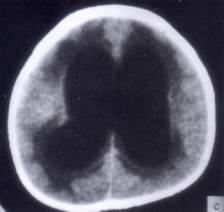

问题 病历摘要:??患者女性,10岁。结核性脑膜炎愈后8月,头痛伴恶心呕吐1周,并渐加重。体检:神清,精神差,反应迟钝,双眼底视神经乳头水肿,双眼外展差,余未见明显异常。 该患者宜采用下列哪种治疗手段?

选项 A.侧脑室-枕大池分流术 B.终板造瘘术 C.侧脑室-腹腔分流术 D.侧脑室-右心房分流术 E.侧脑室-颈静脉分流术 F.腰椎蛛网膜下腔-腹腔分流术 G.脉络丛烧灼术

答案 C